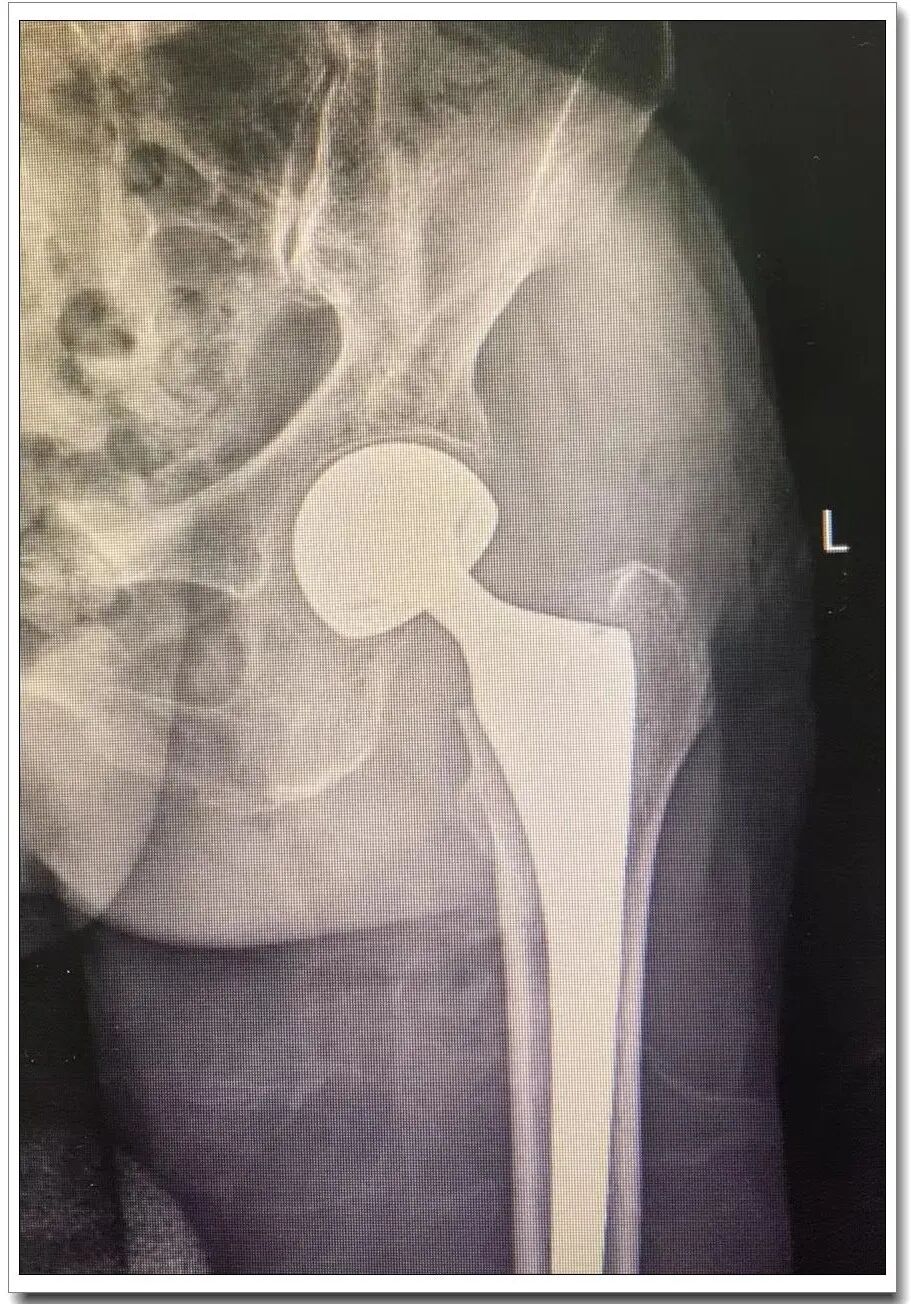

▲股骨颈骨折影像资料

行X线检查后提示左股骨颈骨折。考虑到徐阿婆年龄较大,心肺功能较差,此类手术治疗风险大。但是老年人的股骨颈骨折,如果保守治疗,即相当于放弃治疗,致残率、致死率极高,患者卧床生不如死,给患者及家属带来极大的痛苦和负担。当然选择手术同样会面临很大的风险,需要骨科、内科、麻醉及术后监护、康复、护理各个环节的专业水平和团队合作默契,是对医院整体水平及团队协作精神的考验。